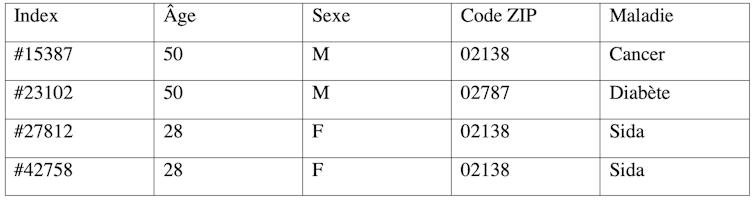

Supposons que nous disposions du jeu de données anonymisées du tableau 1 qui illustre de façon très simplifiée les données ayant conduit à la réidentification du gouverneur du Massachussetts William Weld.

Il est possible, par corrélation entre les deux tableaux, de déduire que le gouverneur W. Weld correspond à l’enregistrement #25587 du tableau 1 (et par déduction qu’il souffre d’un cancer). Cette attaque de réidentification est appelée plus scientifiquement « attaque d’individualisation ».

Quant à l’« attaque par inférence », elle consiste à déduire de certaines valeurs des attributs (âge, sexe, code ZIP) des valeurs pour d’autres attributs (maladie). Par exemple, grâce au tableau 1, on peut déduire que toutes les femmes de 28 ans résidant dans la zone identifiée par le code ZIP 02138, et faisant partie de l’étude car elles ont effectué des soins dans un certain hôpital, souffrent du sida.